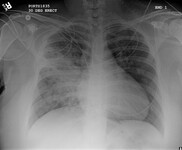

Radiografía de tórax portátil con opacidades bibasales, peor a la derecha que a la izquierda, en un paciente con neumonía adquirida en el hospital

De la colección personal del Dr. F. W. Arnold, División de Enfermedades Infecciosas, Departamento de Medicina, University of Louisville School of Medicine